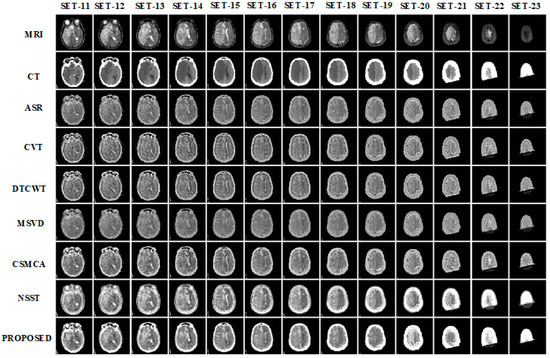

3.1. Subjective Assessment